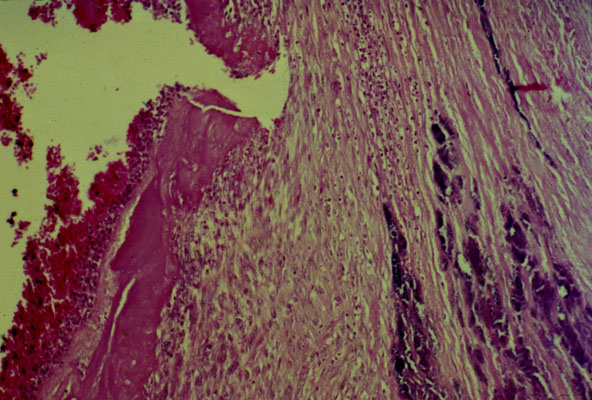

Bacterial endocarditis, micro

Acute bacterial

endocarditis

. The valve is partially covered with

fibrin

and partially ulcerated.